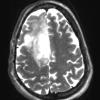

NEOPLASMS (GLIAL)

Astrocytoma, IDH-mutant, WHO Grade 2 (11)